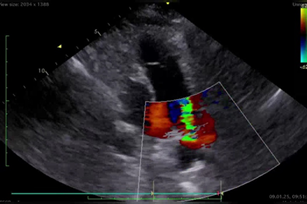

UŞAQLARDA ÜRƏYİN MİTRAL VƏ ÜÇTAYLI ATRİOVENTRİKULYAR QAPAQLARINDA KİÇİK İNKİŞAF ANOMALİYASI ZAMANI MİOKARDIN ELEKTRİK VƏ FUNKSİONAL REMODELLƏŞMƏSİ İ.İ İsayev, Samirə Xanməmmədova, A.İ Mustafayeva, R.R. Məmmədova, B.N. Əsədov

Dərc edilib: AKJ N1 (27) 2025